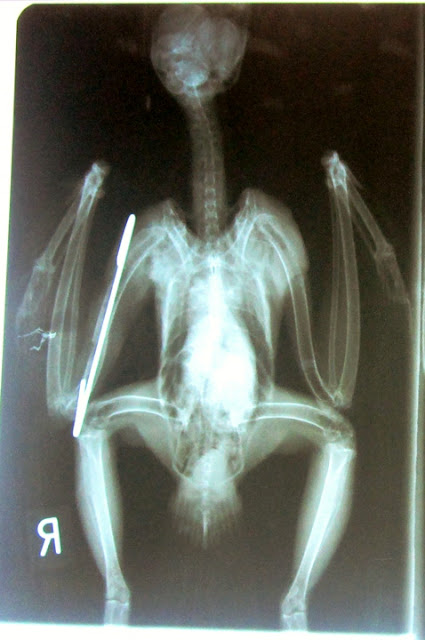

Αυτή τη βδομάδα στάλθηκε από την Άνδρο στην ΑΝΙΜΑ μια

Γερακίνα με ανοιχτό κάταγμα από ατύχημα.

Ο κτηνίατρος της ΑΝΙΜΑ έκανε ήλωση στη φτερούγα και ελπίζουμε για το καλύτερο!

Στις φωτογραφίες:

η Γερακίνα στο κτηνιατρείο έτοιμη για την ακτινογραφία

της μετά την

επέμβαση,

η ακτινογραφία όπου φαίνεται η ήλωση .